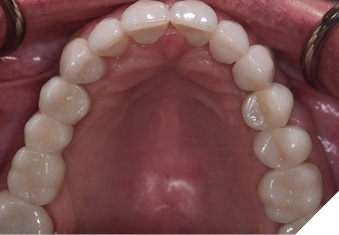

A 65-year-old woman comes to the office with the chief complaint of worn-down teeth, missing teeth, tooth sensitivity, especially on maxillary teeth and TMJ pain. Her past medical history was reviewed and was significant for asthma, insomnia, hypercholesterolemia, hypothyroidism, and anxiety disorder. She denied any sleep disturbances. Her medications included salbutamol, ezetimibe, quetiapine, and levothyroxine. She referred to being allergic to dust and shellfish and sensitive to propofol. She had a right mastectomy in 2014 due to breast cancer. No chemotherapy or radiation was done. Her diet was considered normal, and she denied any consumption of acidic drinks and denied any history of regurgitation. She denied any parafunctional habits during the day. She was using a maxillary transitional partial denture since she had lost some of her teeth due to fracture and caries. No other problems were evidenced. Intraoral exam showed moderate attrition lesions of posterior teeth, porcelain fused to metal crowns on teeth 46 and 47 had the porcelain portion worn down, exposing the metal substructure. Missing teeth included teeth 14,15,16,18,24,28, 36,38,48. Palatal surfaces of maxillary anterior teeth also appeared worn down. An abfraction lesion was found on tooth 23. No carious lesions were found in any of her teeth. Composite restorations on mandibular anterior teeth were chipped or were missing (Figs. 6-11) She also presented with limited mouth opening: 35 mm interincisal distance at maximum opening. There was bilateral pain on palpation of preauricular areas. Her pain was the worst early in the morning which suggested night parafunction. No crepitus, or joint clicking were found.

Fig. 6

Fig. 7

Fig. 8

Fig. 9

Fig. 10

Fig. 11

Articulated diagnostic casts showed very limited to no overjet and 90% of overbite. The wear pattern on the palatal aspect of her maxillary teeth appeared to be secondary to her tight occlusion since mandibular anterior teeth were in close contact with these surfaces with no “room” for protrusive movements. The diagnosis for this patient was: partial edentulism, failing existing restorations and attrition and abfraction secondary to parafunction. We discussed different options, including orthodontics in order to increase her overjet so we could have prosthetic space to restore her worn down teeth. We also discussed tooth replacement options. After a second consultation appointment which she attended with her husband, she decided that she did not want to replace her teeth with removable prosthetics. She also declined referral to an orthodontist. After discussion of multiple options of treatment to address all her chief complaints, her treatment consisted of a full mouth reconstruction with full coverage restorations in Zirconia for teeth 11-13,17,22-23,25-27,32-42, 44-47 and partial coverage restorations with lithium disilicate restoration for teeth 33,34 and 43. Replacement of teeth was achieved with a fixed partial denture to replace tooth 36 and a 3-unit implant supported bridge to replace teeth 24-26. In terms of occlusion, we created a more favorable occlusion with a proper anterior guidance, canine disclusion with more freedom for protrusive movements, which hopefully would decrease the parafunction, and alleviate some of her muscle pain. Before completing the case, the patient spent several weeks with provisional restorations which reflected the increase in vertical dimension of occlusion and the new occlusal scheme. During this trial phase, we assessed comfort, esthetics, function, decrease in pain and speech (Figs. 12-17).